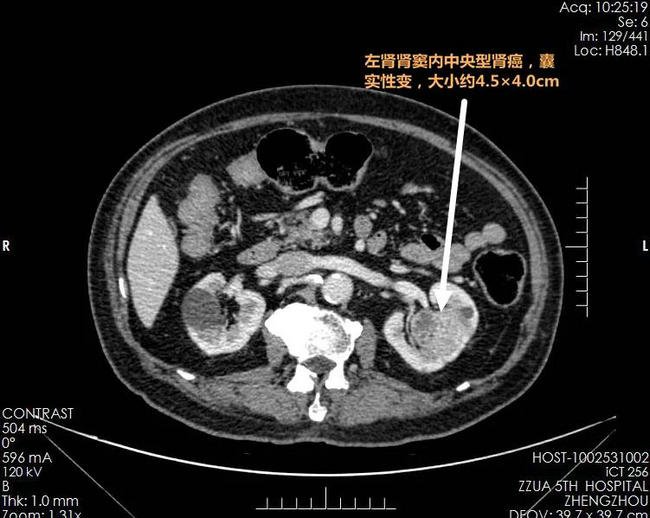

▲ 术前影像检查资料:左肾肾窦处中央型肾癌,左肾下极小肿瘤;双肾萎缩,形态失常(高血压、糖尿病靶器官损害表现)